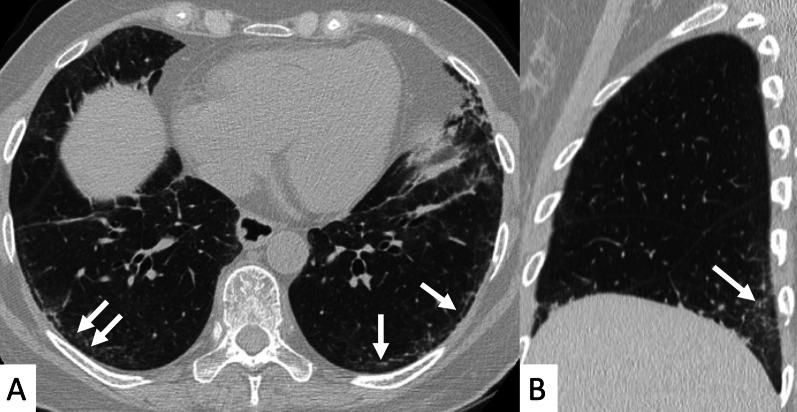

Connective tissue diseases (CTDs) include a spectrum of disorders that affect the connective tissue of the human body; they include autoimmune disorders characterized by immune-mediated chronic inflammation and the development of fibrosis. Lung involvement can be misdiagnosed, since pulmonary alterations preceded osteo-articular manifestations only in 20% of cases and they have no clear clinical findings in the early phases. All pulmonary structures may be interested: pulmonary interstitium, airways, pleura and respiratory muscles. Among these autoimmune disorders, rheumatoid arthritis (RA) is characterized by usual interstitial pneumonia (UIP), pulmonary nodules and airway disease with air-trapping, whereas non-specific interstitial pneumonia (NSIP), pulmonary hypertension and esophageal dilatation are frequently revealed in systemic sclerosis (SSc). NSIP and organizing pneumonia (OP) may be found in patients having polymyositis (PM) and dermatomyositis (DM); in some cases, perilobular consolidations and reverse halo-sign areas may be observed. Systemic lupus erythematosus (SLE) is characterized by serositis, acute lupus pneumonitis and alveolar hemorrhage. In the Sjögren syndrome (SS), the most frequent pattern encountered on HRCT images is represented by NSIP; UIP and lymphocytic interstitial pneumonia (LIP) are reported with a lower frequency. Finally, fibrotic NSIP may be the interstitial disease observed in patients having mixed connective tissue diseases (MCTD). This pictorial review therefore aims to provide clinical features and imaging findings associated with autoimmune CTDs, in order to help radiologists, pneumologists and rheumatologists in their diagnoses and management.

结缔组织病(CTDs)包括一系列影响人体结缔组织的疾病;它们包括以免疫介导的慢性炎症和纤维化发展为特征的自身免疫性疾病。肺部受累可能会被误诊,因为肺部改变仅在20%的病例中先于骨关节炎表现出现,且在早期阶段没有明确的临床发现。所有肺部结构都可能受累:肺间质、气道、胸膜和呼吸肌。在这些自身免疫性疾病中,类风湿关节炎(RA)的特征是普通型间质性肺炎(UIP)、肺结节和伴有空气潴留的气道疾病,而系统性硬化症(SSc)常表现为非特异性间质性肺炎(NSIP)、肺动脉高压和食管扩张。NSIP和机化性肺炎(OP)可见于多发性肌炎(PM)和皮肌炎(DM)患者;在某些情况下,可观察到小叶周围实变和反晕征区域。系统性红斑狼疮(SLE)的特征是浆膜炎、急性狼疮性肺炎和肺泡出血。在干燥综合征(SS)中,HRCT图像上最常见的表现是NSIP;UIP和淋巴细胞间质性肺炎(LIP)的报道频率较低。最后,纤维化NSIP可能是混合性结缔组织病(MCTD)患者中观察到的间质性疾病。因此,本图像综述旨在提供与自身免疫性CTDs相关的临床特征和影像学表现,以帮助放射科医生、呼吸科医生和风湿病科医生进行诊断和管理。